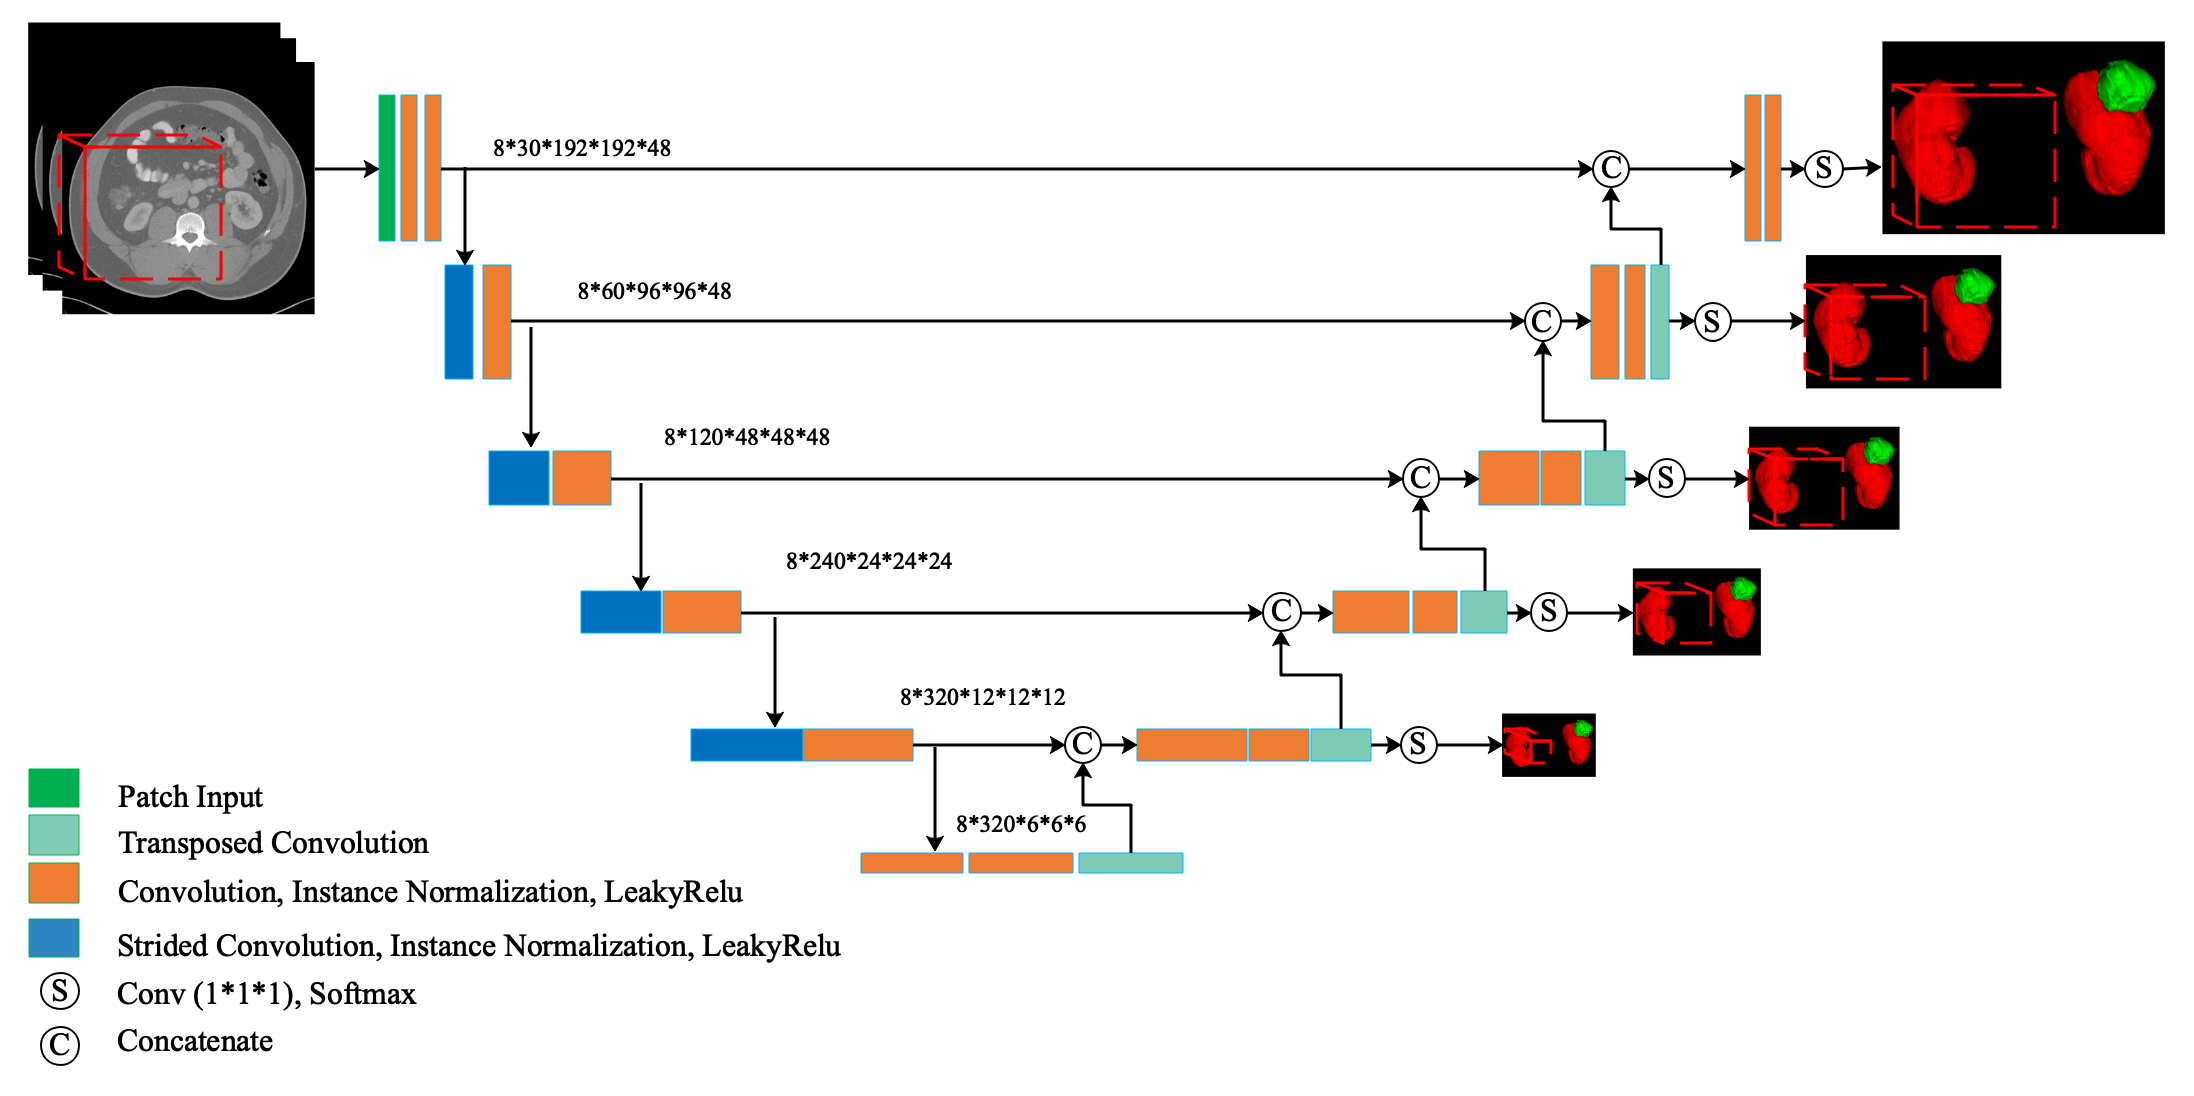

We designed our network based on 3D U-Net [7]. The framework is shown as Fig. 1. This multi scale supervised network makes prediction from different layers of decoder pathway, unlike classical 3D U-Net only predicts from the last layer. These segment outputs would be compared with corresponding resolution labels and then used to calculate the final loss function. Such supervision encourages the network to predict correctly from the low-resolution feature maps which will be up-sampled to be full resolution feature maps.